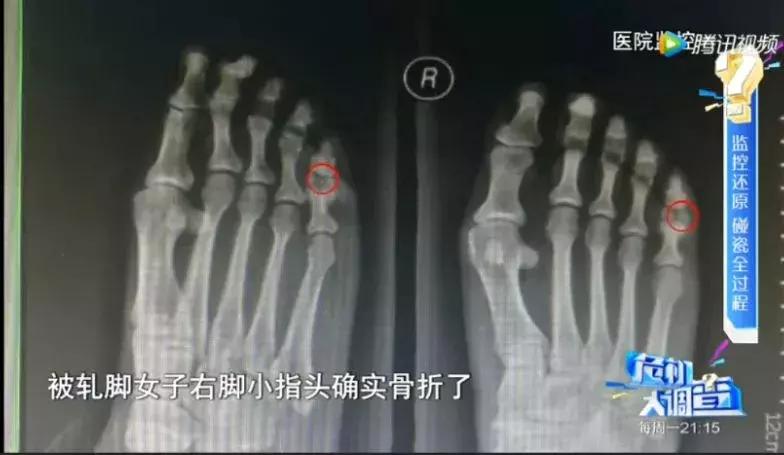

这名碰瓷女子也不是来假的,送往医院后发现脚趾确实骨折了。但事后经调查查明,她是事前用木槌砸断自己的脚趾!